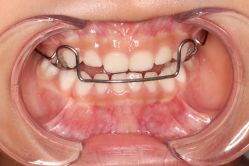

• -青苗儿童口腔(长楹天街购物中心)

相册

晔子_6763 上传于 20-09-20 | 报错